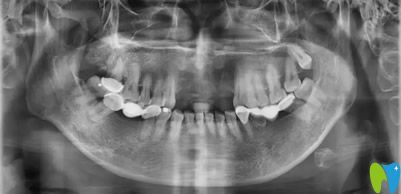

種植牙齒前拍片檢查

從全景和CBCT片顯示,路女士前牙區(qū)牙槽骨較薄,種植體難以“立足”,而且前牙承擔(dān)面部美觀功能,對(duì)后期的修復(fù)體要求比較高。綜合考慮后,孔主任為她制定了“以三抵五”的個(gè)性化種牙方案:在前牙缺失區(qū)域種植3顆骨結(jié)合性、身材小巧”的瑞士百丹特種植體,再利用植體做支點(diǎn),安上5顆全瓷橋修復(fù)體。路女士對(duì)孔醫(yī)生為自己制定的修復(fù)方案相當(dāng)滿意。很快,孔醫(yī)生就為她種下了3顆植體。